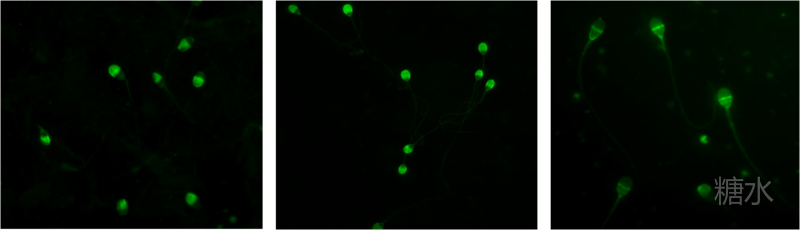

五、 精液伊红-苯胺黑染色:精子存活率可通过评估精子细胞膜的完整程度来确定,活的精子细胞膜完整不能被伊红着色,由此可得出精子存活率。检测精子活率,对于弱精子症、不动精子症等病例有重要意义。

六 、低渗肿胀试验(简称:HOS):检测精子存活率的另一种方法,只有细胞膜完整的精子(活精子)能够在低渗溶液中膨胀,故可根据肿胀的精子的百分率得出精子存活率。检测精子活率,对于弱精子症、不动精子症等病例有重要意义。